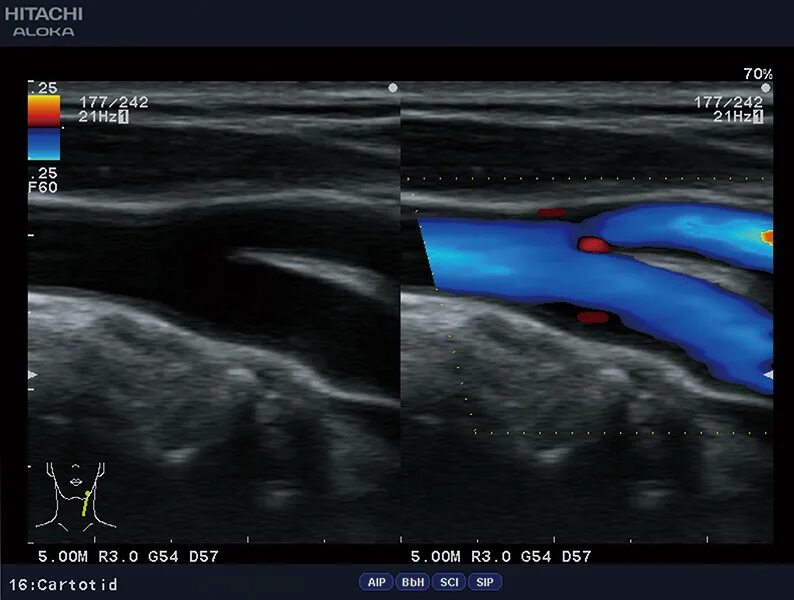

Сделать узи сонной артерии